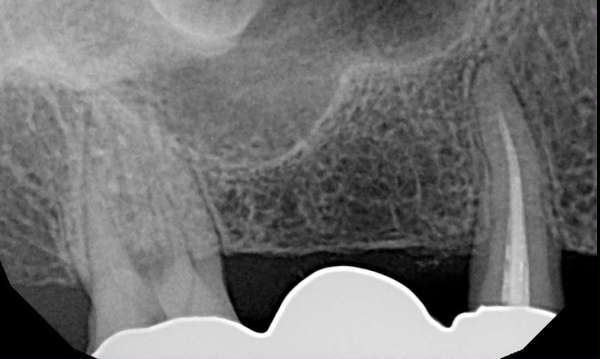

Anchor tooth for the patient's bridge failed and had to be extracted. Patient had two implants placed rather than replacing with a longer-spanning bridge.